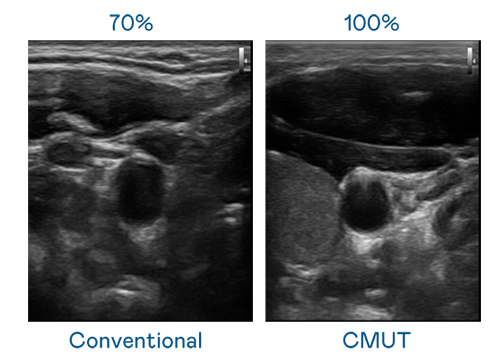

CMUT 技术是一种用电容式微机电元件来产生超音波讯号的技术。与传统 PZT 压电式技术相比,CMUT 频宽增加 30%,更宽频的超音波讯号让影像解析度大幅提升,是实现高影像品质医疗超音波扫描、促进精准医疗发展的关键技术。

大频宽带来超清晰影像

超音波影像的解析度高低,首先取决于探头能发出的讯号频宽。天美mv乌鸦mv星空mv果冻mv二区麻花 CMUT 可提供高清晰的超音波讯号,提供高频宽、高灵敏度、影像纹理细节更高的超音波影像,协助医护人员缩短影像判读时间及利用精准的医疗影像进行诊断。